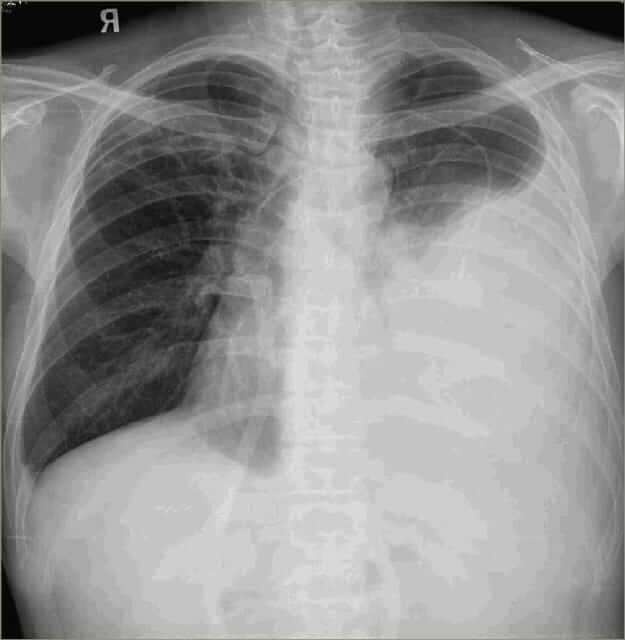

CXR Report: Large, opacified left hemithorax consistent with a large pleural effusion. There is a contralateral mediastinal shift. The upper mediastinum appears widened.

CXR Report: Large, opacified left hemithorax consistent with large pleural effusion. Contralateral mediastinal shift. Upper mediastinum appears widened.

CXR Report: Large, opacified left hemithorax consistent with large pleural effusion. Contralateral mediastinal shift. Upper mediastinum widened.